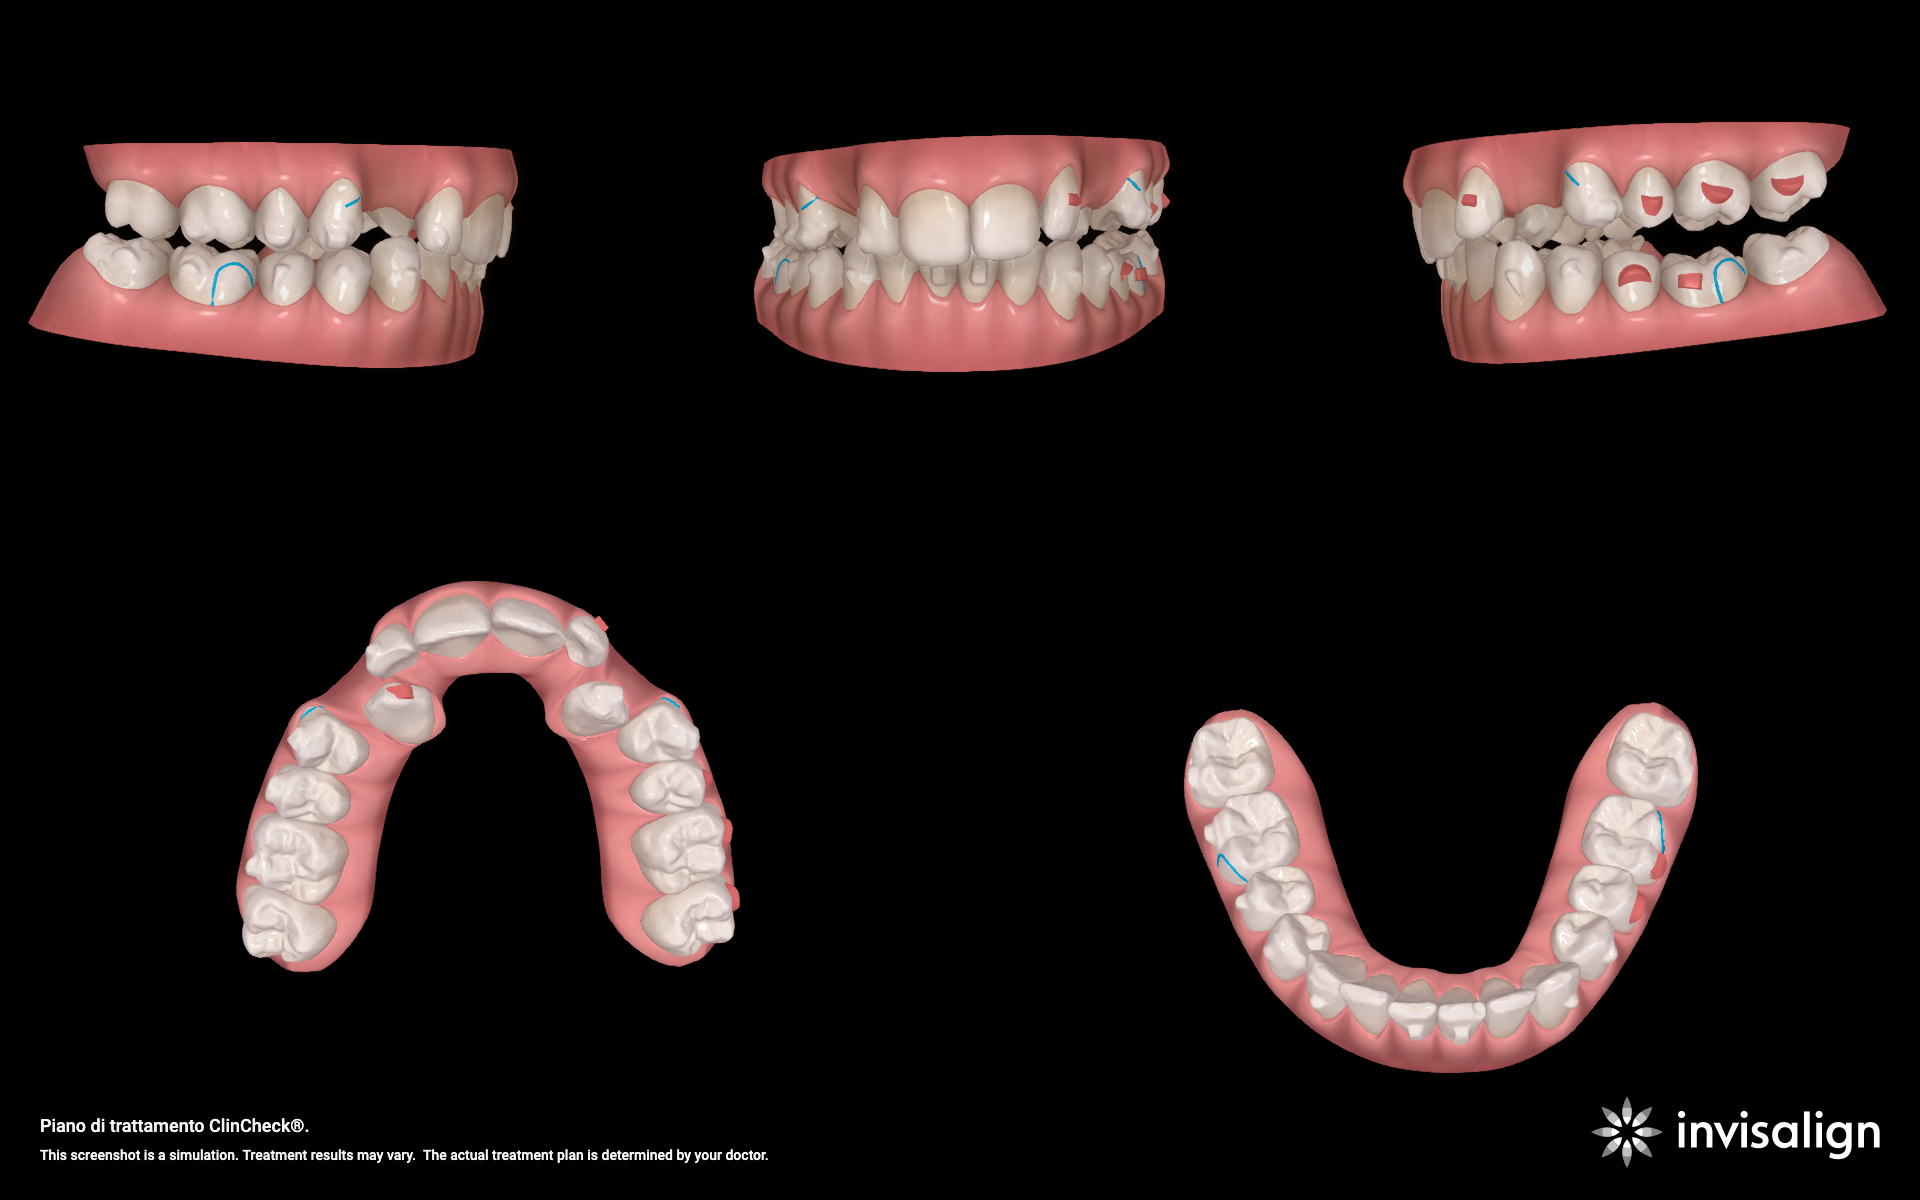

Integrazione digitale e allineatori

Dopo il recupero palatale, è iniziata la fase con allineatori trasparenti, sfruttando il software ClinCheck® Pro e l'integrazione dei dati della CBCT.

Pianificazione e criticità

- Torque: necessità di recuperare il torque positivo sugli incisivi superiori.

- Classe: correzione sagittale tramite distalizzazione sequenziale ( per creare spazio ai canini) e Jump sagittale.

- Gestione del 23: utilizzo di un attachment rettangolare (secondo protocollo Capuozzo et al.) per migliorare il controllo del torque durante la traslazione palato-vestibolare.

- Gestione del 13: data la posizione estremamente palatale, inizialmente non è stato incluso nell'allineatore. È stato avvicinato alla corretta posizione vestibolare mediante un elastico a cavaliere.

Risultati finali

Il trattamento si è concluso con successo, raggiungendo tutti gli obiettivi prefissati:

- stabilità sagittale: prima classe molare e canina.

- Verticalità: risoluzione del morso coperto con overbite e overjet ideali.

- Estetica e funzione: torque degli incisivi normalizzato e corretta inclinazione degli incisivi inferiori, utilizzata per risolvere l'affollamento e limitaare la necessità di IPR.

L'integrazione tra la biomeccanica tradizionale (leve in TMA) e l'ortodonzia digitale (allineatori e CBCT) permette di gestire casi complessi di inclusione con estrema sicurezza. Il protocollo Canine First si conferma una scelta vincente per minimizzare i rischi iatrogeni, mentre la tecnologia ClinCheck® Pro garantisce una predicibilità altrimenti difficile da ottenere in casi di II Classe Divisione 2.